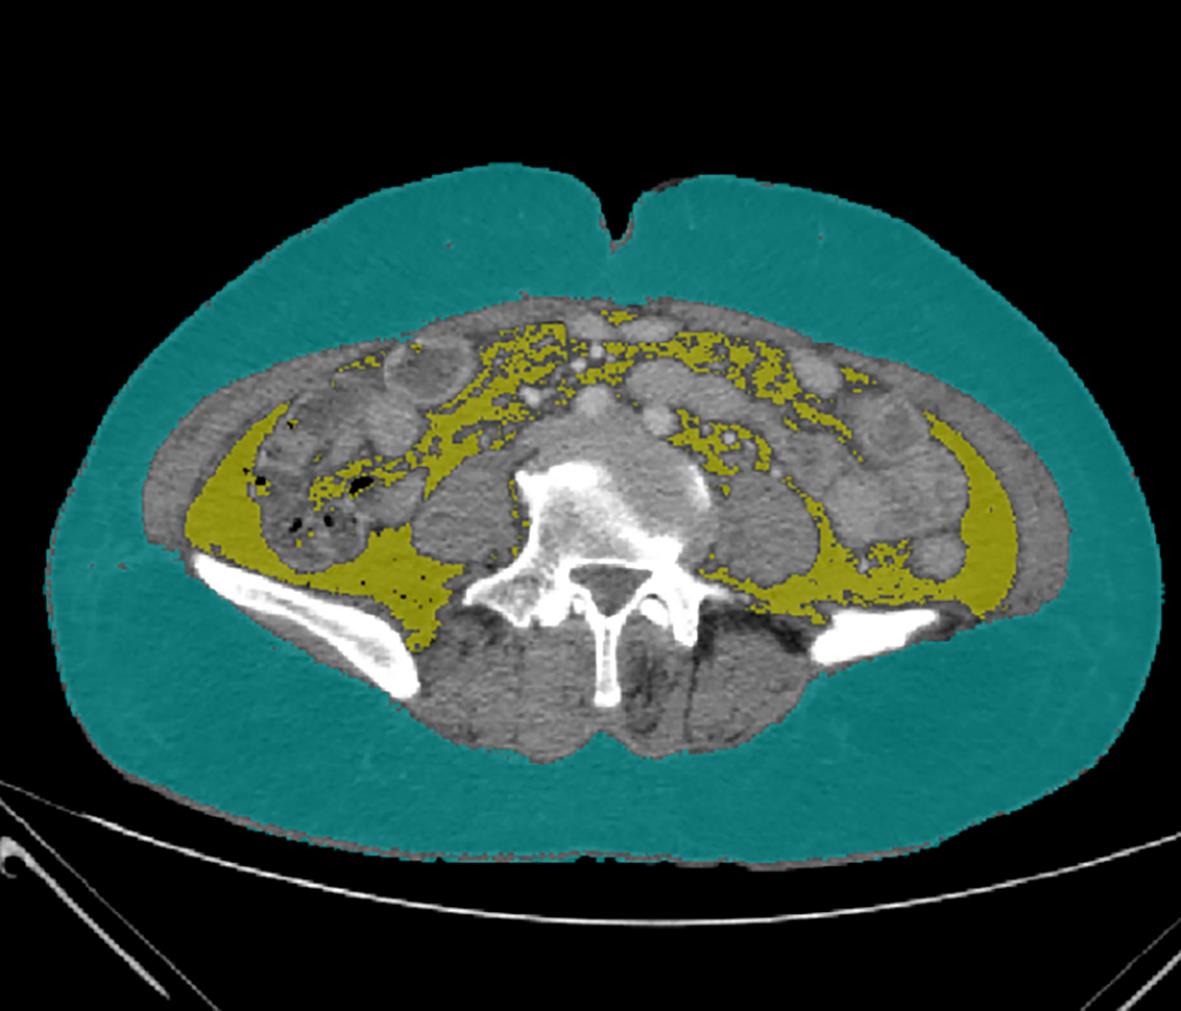

Clinical features of bone mass loss in liver cirrhosis and its association with sarcopenia

Qiu JIN, Jing YANG, Honglin MA, Zhenghao SUN, Qingqing LIU, Shaoshan HU, Pingju LI

2023, 39(12): 2831-2838. DOI: 10.3969/j.issn.1001-5256.2023.12.013

Abstract(1009) HTML (293) PDF (750KB)(95)

Abstract:

Objective  To investigate the influence of sarcopenia on bone mass loss, the risk factors for bone mass loss in liver cirrhosis, and the correlation between body composition and bone mineral density (BMD) by comparing the clinical features of bone mass loss in patients with liver cirrhosis.  Methods  A total of 92 patients who were hospitalized and diagnosed with liver cirrhosis in Department of Gastroenterology, The Second Affiliated Hospital of Kunming Medical University, from April to December of 2022 were enrolled, and based on the results of dual-energy X-ray absorptiometry, they were divided into bone mass loss group (osteopenia/osteoporosis) with 57 patients and normal bone mass group with 35 patients. The two groups were compared in terms of general data, laboratory examination, imaging data, and body composition analysis. The independent samples t-test or the Mann-Whitney U test was used for comparison of continuous data between two groups, and the chi-square test or the continuity correction chi-square test was used for comparison of categorical data between two groups; Pearson correlation analysis and Spearman correlation analysis were used to investigate correlation; a binary logistic regression analysis was used to investigate the risk factors for bone mass loss in liver cirrhosis.  Results  Compared with the normal bone mass group, the bone mass loss group had significantly higher age (t=-3.597, P<0.05), proportion of female patients (χ2=8.393, P<0.05), N-terminal middle molecular fragment of osteocalcin (N-MID) (Z=-3.068, P<0.05), β isomer of C-terminal telopeptide of type I collagen (β-CTX) (t=-2.784, P<0.05), and proportion of patients with sarcopenia (χ2=13.884, P<0.05) and significantly lower calcitonin (CT) (Z=-2.340, P<0.05) and L3 skeletal muscle index (L3-SMI) (t=4.621, P<0.05). Compared with the normal bone mass group, the bone mass loss group had significantly lower total muscle mass (Z=-2.952, P<0.05), right upper limb muscle mass (Z=-2.929, P<0.05), left upper limb muscle mass (Z=-2.680, P<0.05), right lower limb muscle mass (Z=-3.366, P<0.05), left lower limb muscle mass (Z=-3.374, P<0.05), presumed bone mass (t=2.842, P<0.05), body water mass (Z=-2.779, P<0.05), basal metabolic rate (BMR) (Z=-3.153, P<0.05), and BMD of L1— L4 and femoral neck (t=9.789, t=10.280, t=10.832, Z=-7.298, t=8.945, all P<0.05). Total muscle mass, muscle mass of trunk and limbs, presumed bone mass, BMR, and body water mass in body component analysis were positively correlated with L1 — L4 BMD and femoral neck BMD (all P<0.05), and fat mass was positively correlated with L1 — L4 BMD (all P<0.05). Sarcopenia (odds ratio [OR]=8.737, 95% confidence interval [CI]: 2.237 — 34.129, P=0.002), age (OR=1.094, 95%CI: 1.019 — 1.175, P=0.013), and N-MID (OR=1.095, 95%CI: 1.019 — 1.176, P=0.014) were independent risk factors for bone mass loss in patients with liver cirrhosis.  Conclusion  Old age, female sex, sarcopenia, elevated N-MID, elevated β-CTX, reduction in CT, low muscle mass, low presumed bone mass, low BMR, and low body water mass are the features of bone mass loss in patients with liver cirrhosis, and sarcopenia, age, and N-MID are independent risk factors for bone mass loss in patients with liver cirrhosis. Detailed assessment of body composition changes can help to identify abnormal BMD in patients with liver cirrhosis.